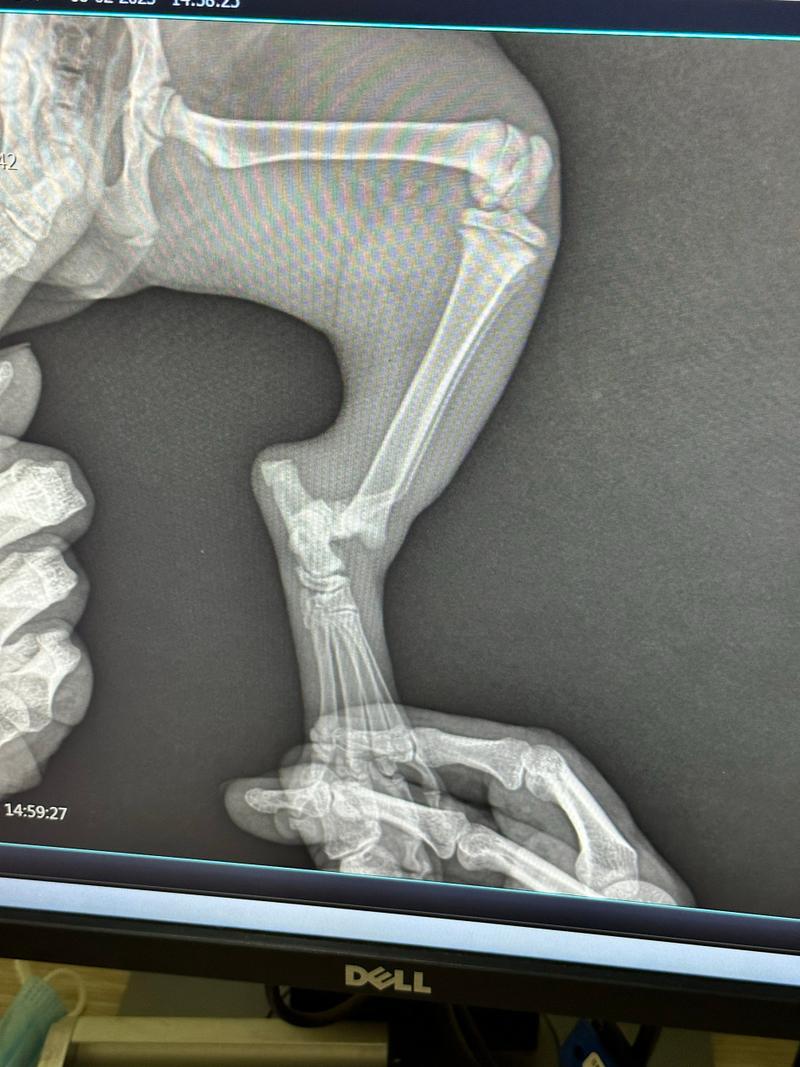

猫咪前腿弯曲的原因多种多样,从轻微的扭伤到严重的骨折,甚至可能是先天性的骨骼畸形。你是否想过,猫咪前腿弯曲究竟是怎么回事?是缺钙导致的骨骼变形,还是先天性的基因问题?又或者是腿部受伤后的后遗症?这些问题的答案,关系到猫咪的治疗和康复。了解病因,才能有的放矢,为猫咪提供最有效的帮助。

根据初步判断的结果,采取不同的应对措施,核心是“不加重损伤”。对于紧急情况,如骨折、脱臼、神经问题,禁止强行抱持,可用硬纸板制作“简易夹板”或用毛巾包裹猫咪,保持身体固定,立即送医。对于轻微外伤,可用生理盐水冲洗伤口,涂抹宠物专用碘伏,再用无菌纱布包扎,并限制活动。

4. 猫前腿手弯了是骨折么_百度知道